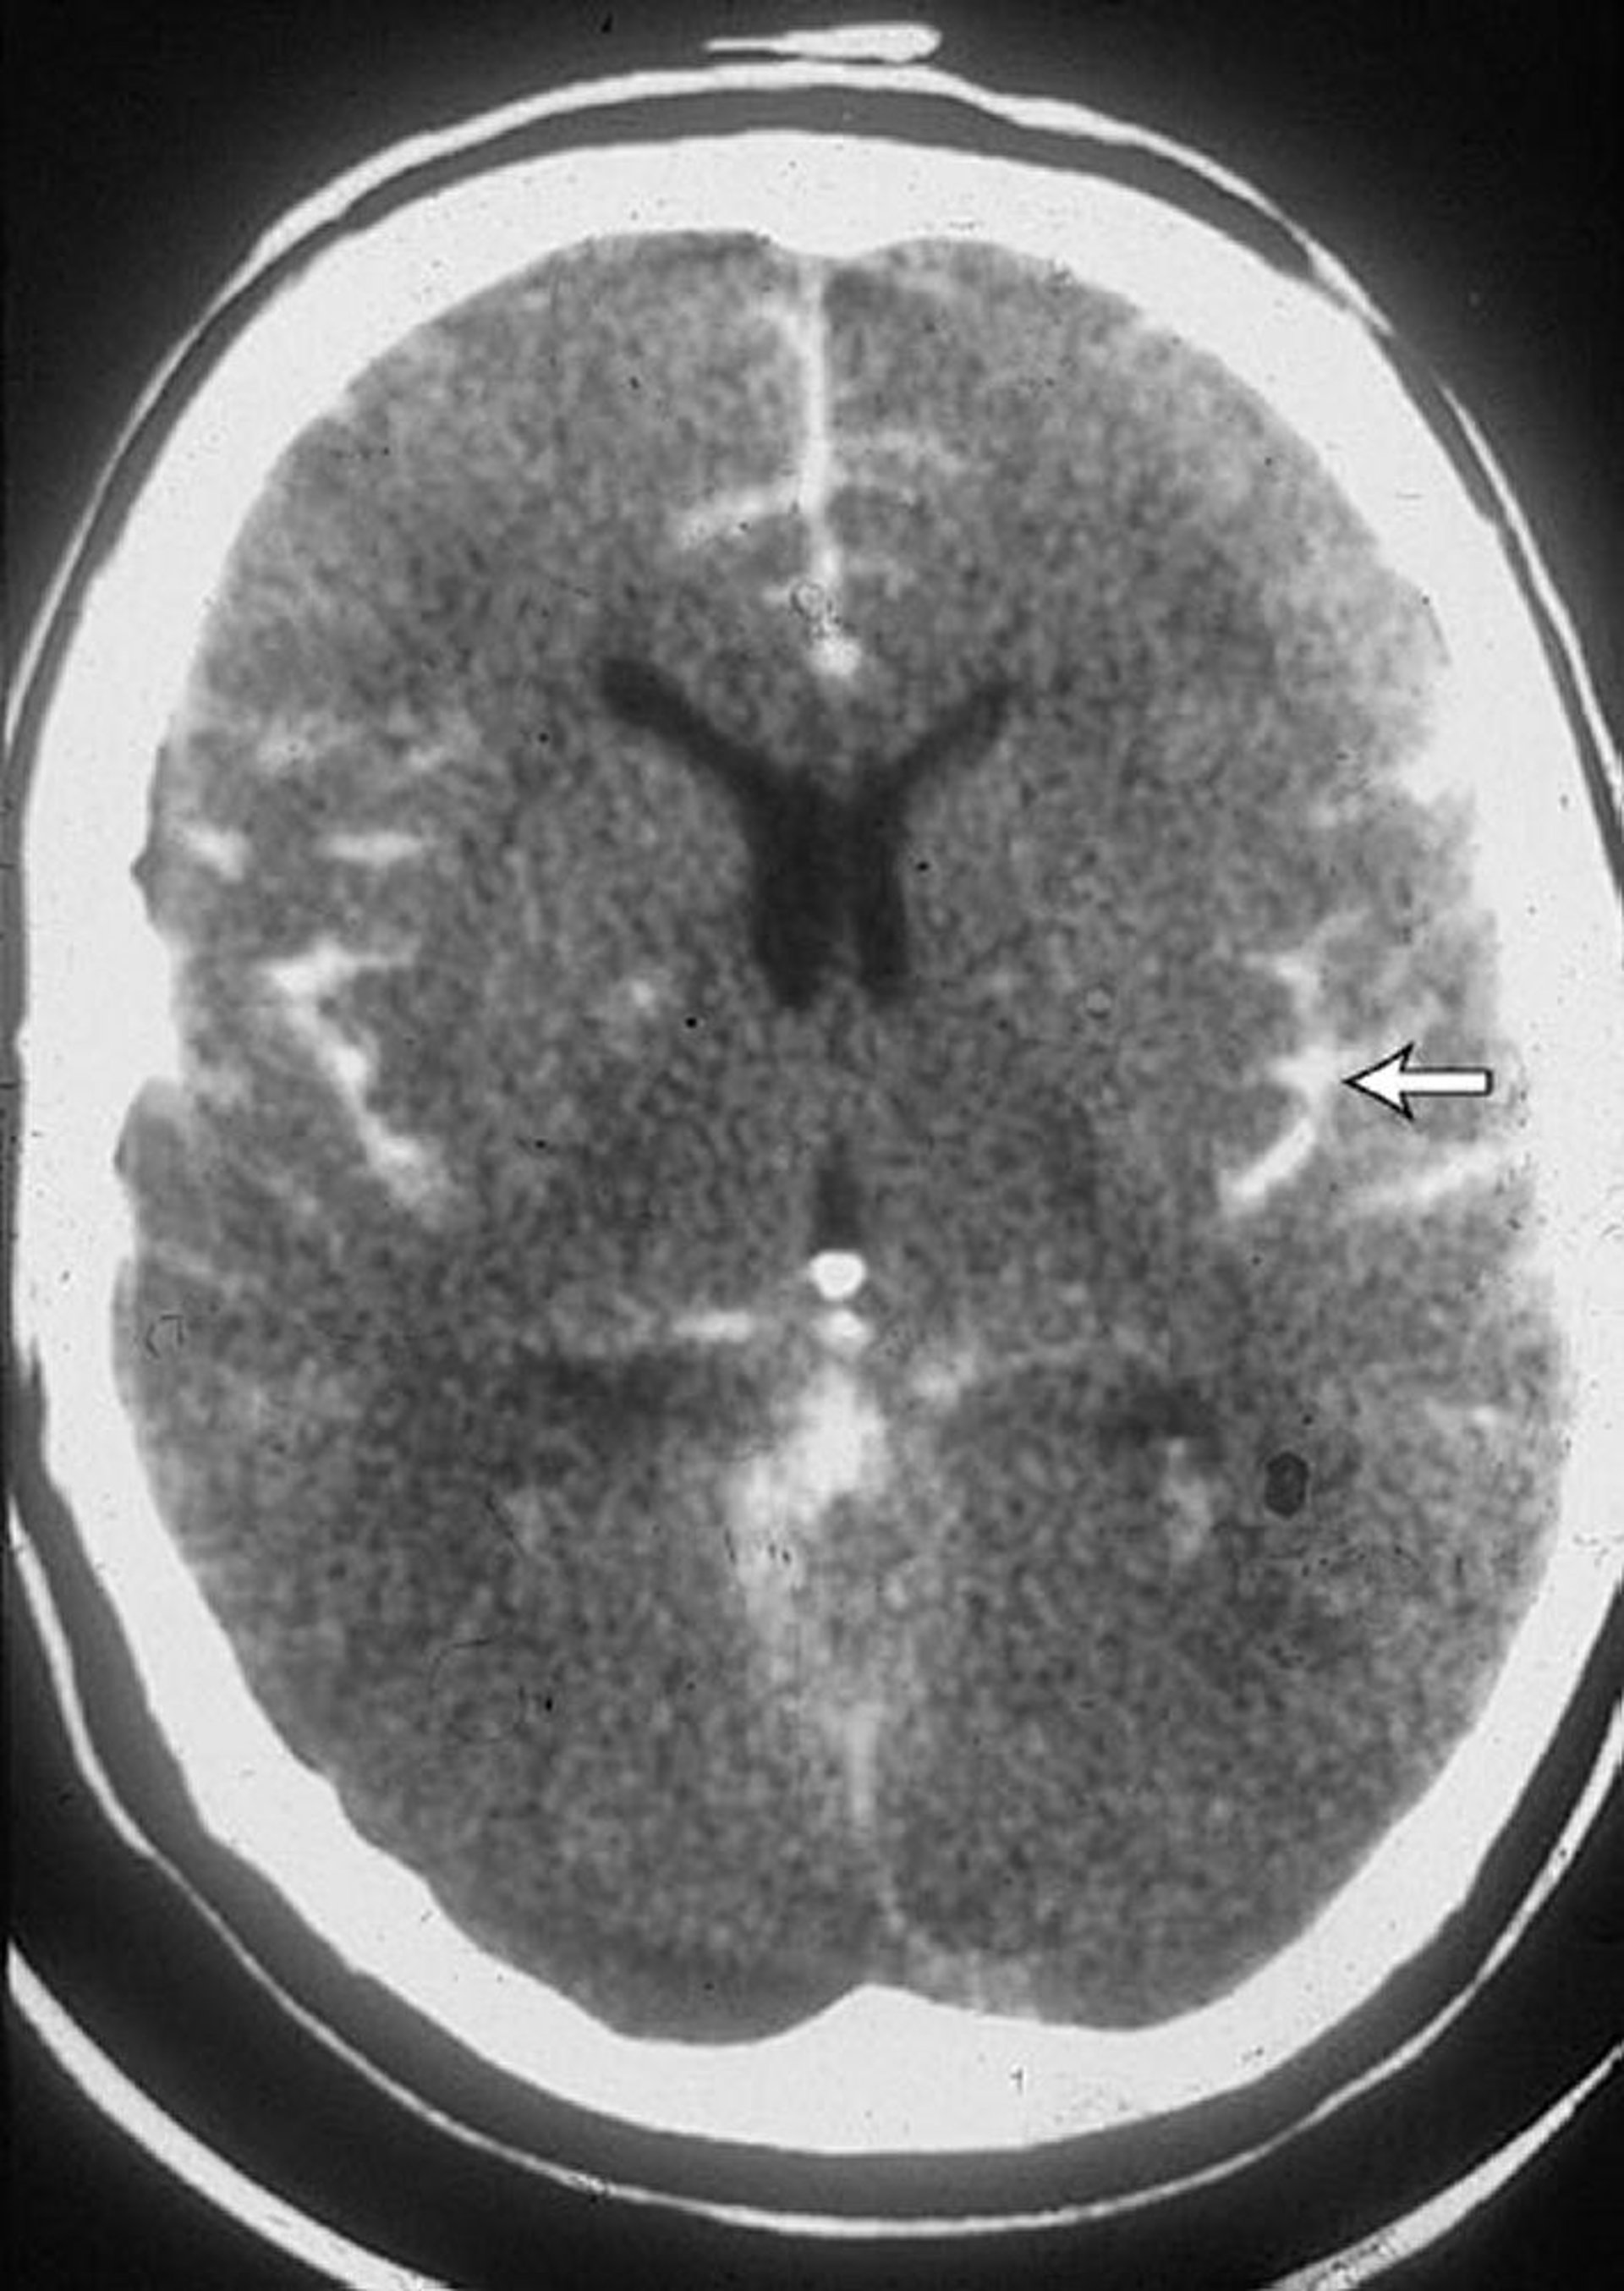

Hemorragia subaracnoidea

TC de um paciente com hemorragia subaracnoidea mostra sangue nos sulcos (seta). Frequentemente também é visto sangue nos ventrículos.

By permission of the publisher. From Lenaerts M, Couch J. In Atlas of Clinical Neurology. Edited by RN Rosenberg. Philadelphia, Current Medicine, 2002.